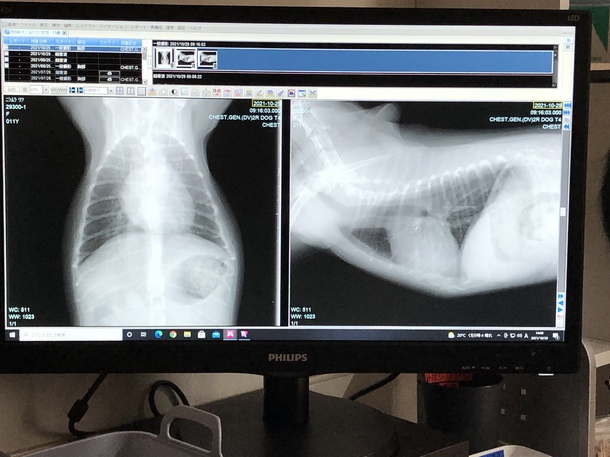

今日は3ヶ月検診でした!!

レントゲン、エコー、心電図、血液検査等全て検査しました!!

結果は、全て正常内で先生から良好と診断されました!